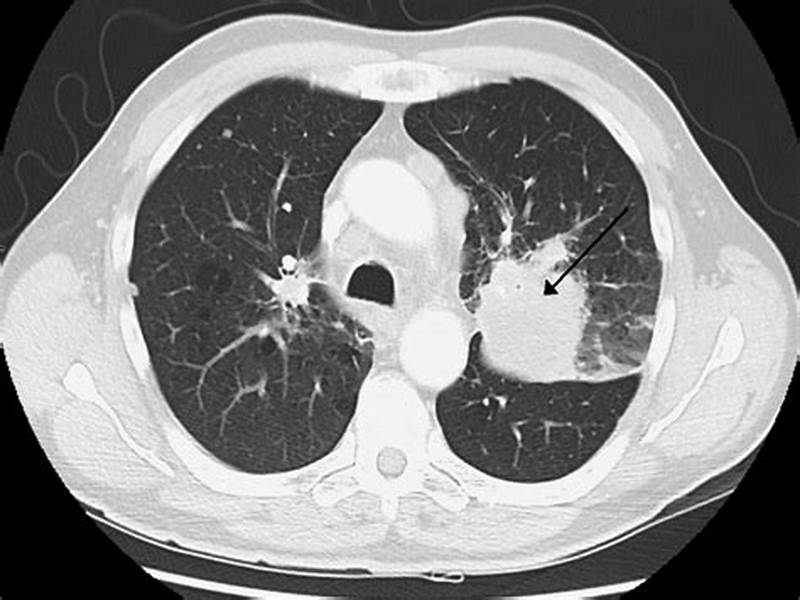

低劑量CT (low-dose computed tomography,LDCT) 發現早期肺癌的敏感度是常規胸片的4-10倍,可以檢出早期周圍型肺癌。

國際早期肺癌行動計劃數據顯示,LDCT年度篩查能發現85%的Ⅰ期周圍型肺癌,術后10年預期生存率可達92%。

美國全國肺癌篩查試驗證明, LDCT 篩查可降低 20% 的肺癌死亡率,是目前最有效的肺癌篩查工具。